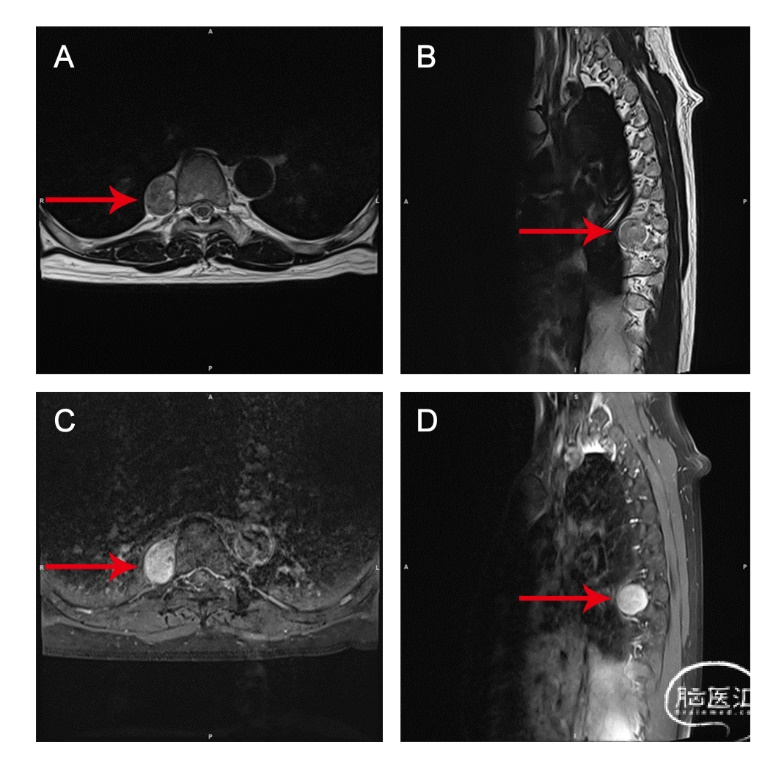

患者男,64岁,体检发现胸腔内椎旁占位1年,无神经体征,术前MRI显示T8椎旁占位。

术后MRI显示肿瘤完全切除,三维重建图像显示了切除后的骨性结构。